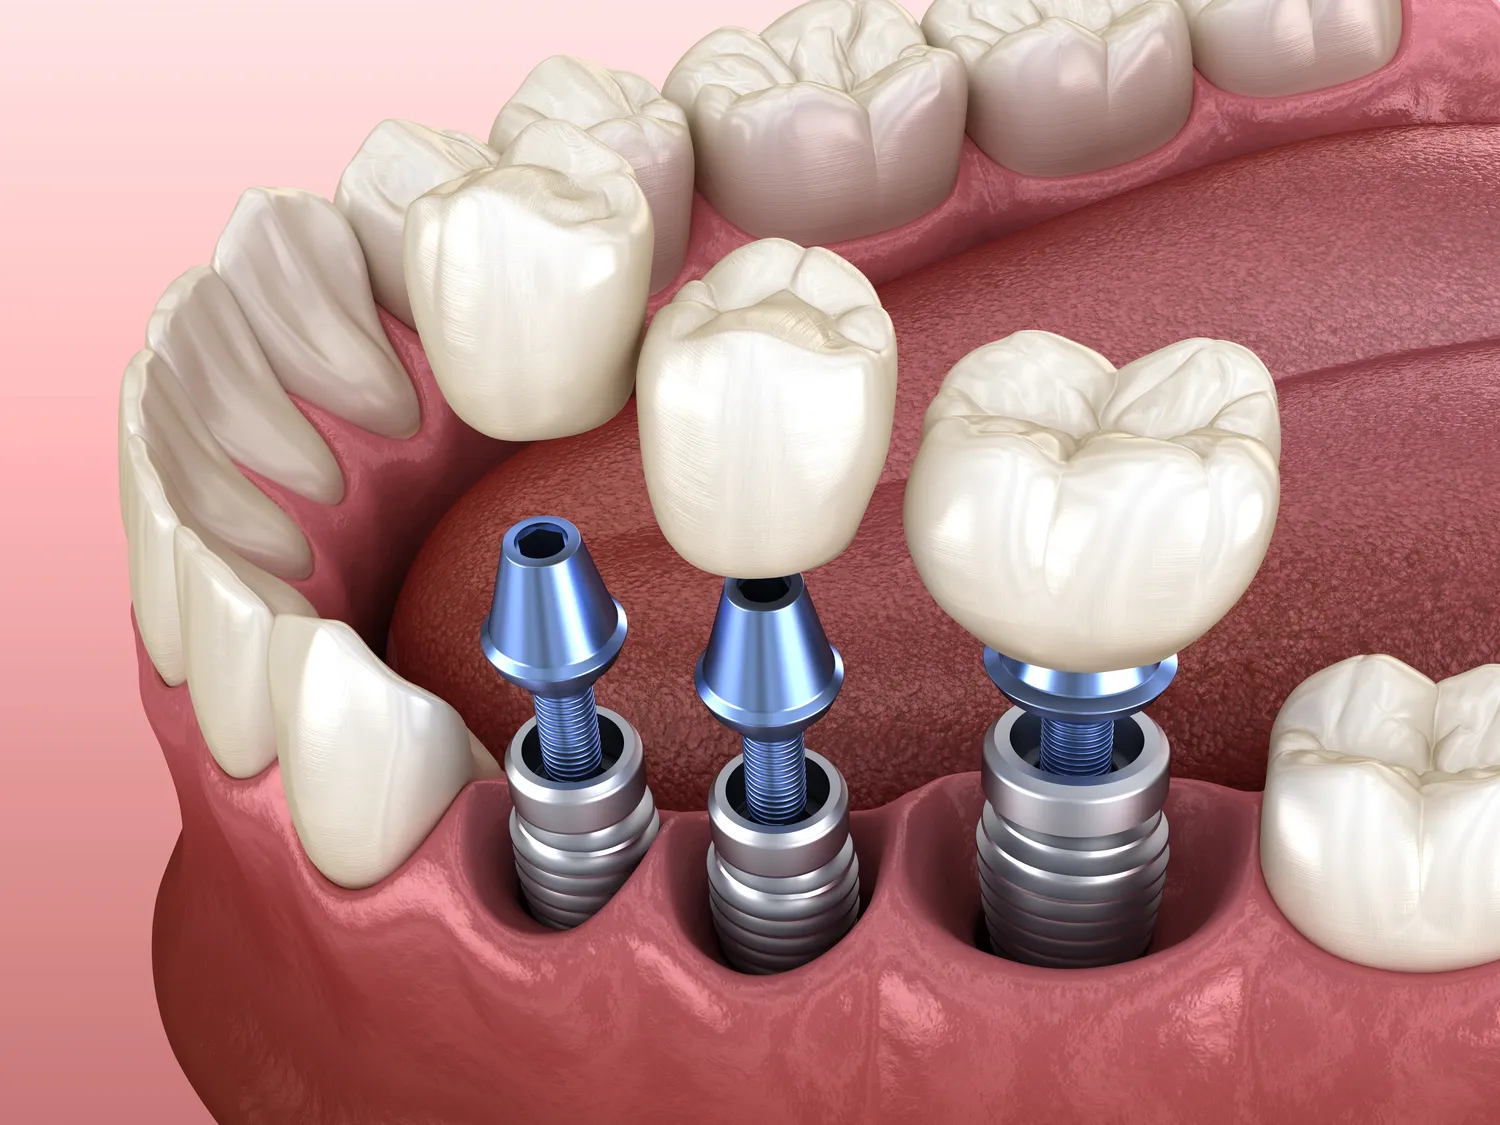

Proces zakupu i wszczepienia implantów zębowych w Warszawie składa się z kilku kluczowych etapów, które mają na celu zapewnienie pacjentowi jak najlepszego efektu końcowego. Pierwszym krokiem jest konsultacja ze specjalistą, podczas której lekarz oceni stan zdrowia jamy ustnej pacjenta oraz przeprowadzi szczegółowy wywiad medyczny. Na podstawie tych informacji lekarz podejmie decyzję o konieczności wykonania dodatkowych badań diagnostycznych, takich jak zdjęcia rentgenowskie czy tomografia komputerowa. Po dokładnej ocenie stanu uzębienia lekarz zaproponuje odpowiednią metodę leczenia oraz omówi szczegóły dotyczące zabiegu. Następnie następuje etap wszczepienia implantu, który zazwyczaj odbywa się w znieczuleniu miejscowym. Po wszczepieniu implantu konieczne jest odczekanie kilku miesięcy na proces osteointegracji, czyli połączenia implantu z kością szczęki. Po tym czasie można przystąpić do wykonania korony protetycznej, która zostanie zamocowana na implancie.

Proces gojenia po wszczepieniu implantów zębowych jest kluczowym etapem leczenia i może trwać różnie w zależności od wielu czynników. Zazwyczaj czas gojenia wynosi od kilku tygodni do kilku miesięcy. Po pierwszym etapie zabiegu następuje proces osteointegracji, czyli połączenia implantu z kością szczęki. Ten proces jest niezwykle istotny dla stabilności implantu i trwa zazwyczaj od 3 do 6 miesięcy. W przypadku pacjentów z dobrą jakością kości oraz przestrzegających zaleceń lekarza czas ten może być krótszy. Warto jednak pamiętać, że każdy organizm jest inny i czas gojenia może się różnić w zależności od indywidualnych predyspozycji oraz stanu zdrowia pacjenta. Po zakończeniu procesu osteointegracji można przystąpić do wykonania korony protetycznej, co wiąże się z kolejnymi wizytami u dentysty oraz dalszymi etapami leczenia.